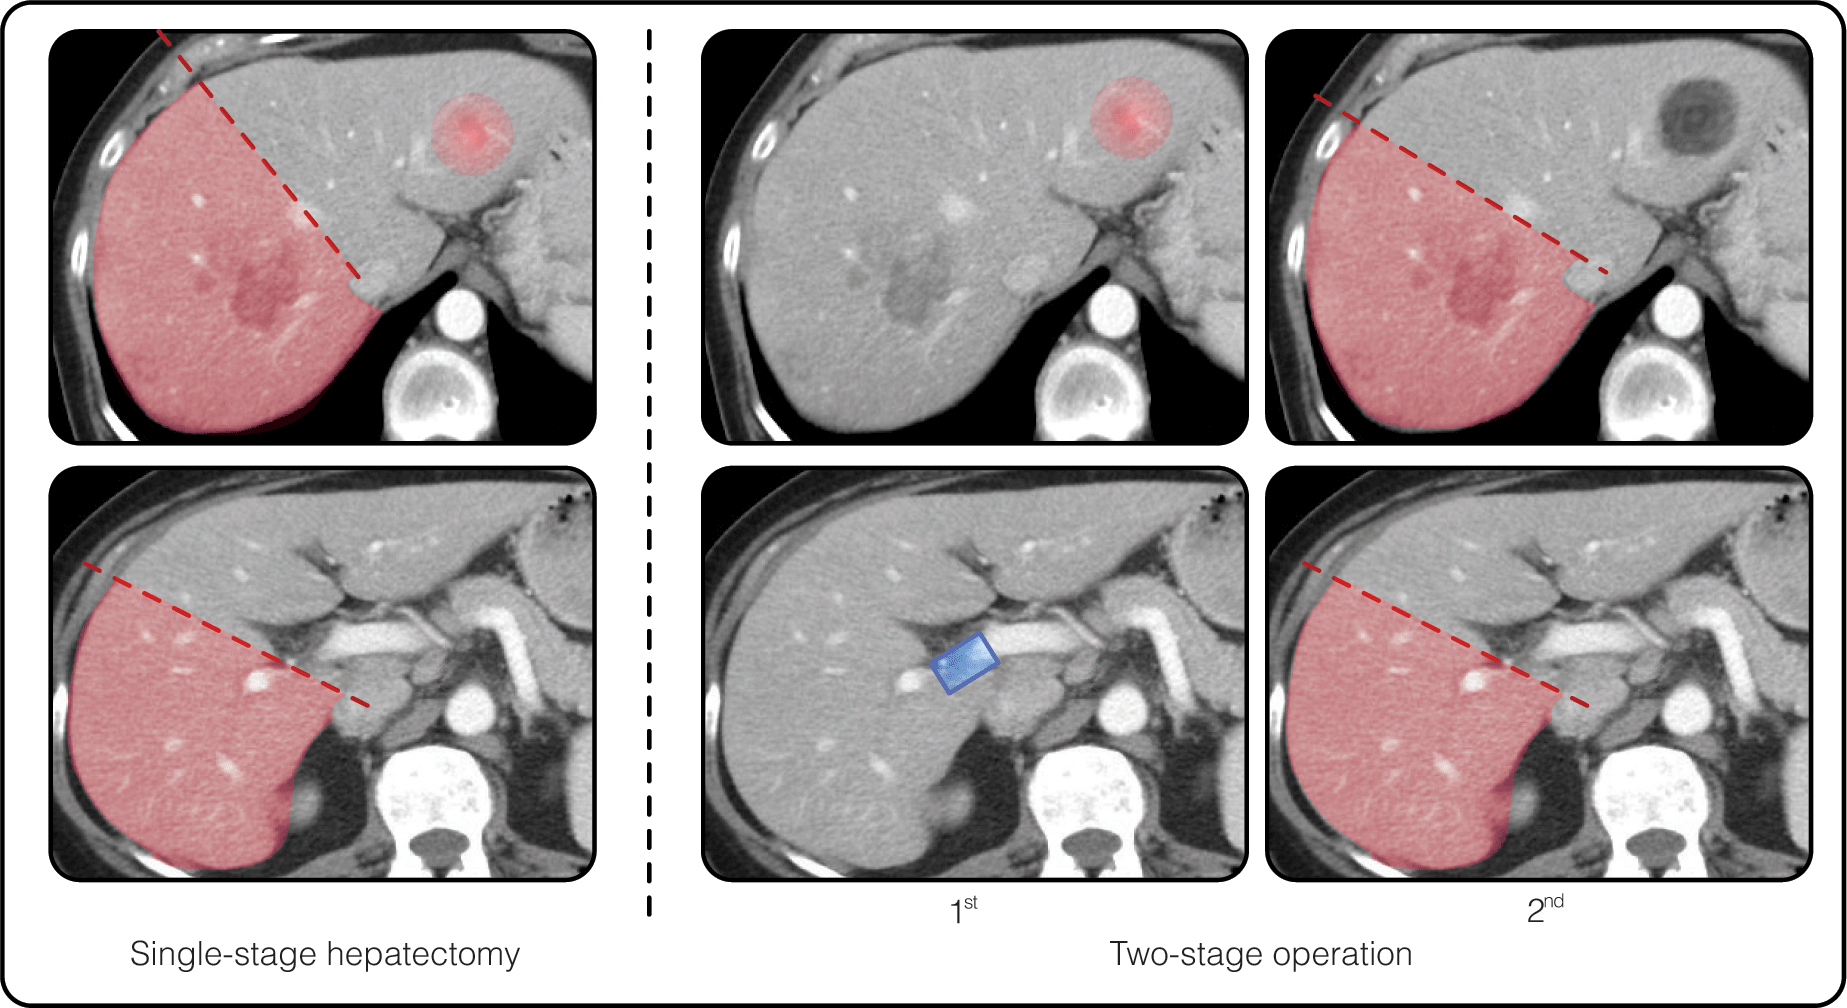

- Safety of liver resection through improvements in perioperative management and adoption of liver-parenchyma-sparing techniques.

- Downstaging strategy for unresectable tumors via systemic or liver-directed chemotherapy have increased surgical candidacy.

- Prolonged overall survival related to expanded use of surgery, effective chemotherapy, and treatment of recurrent disease.